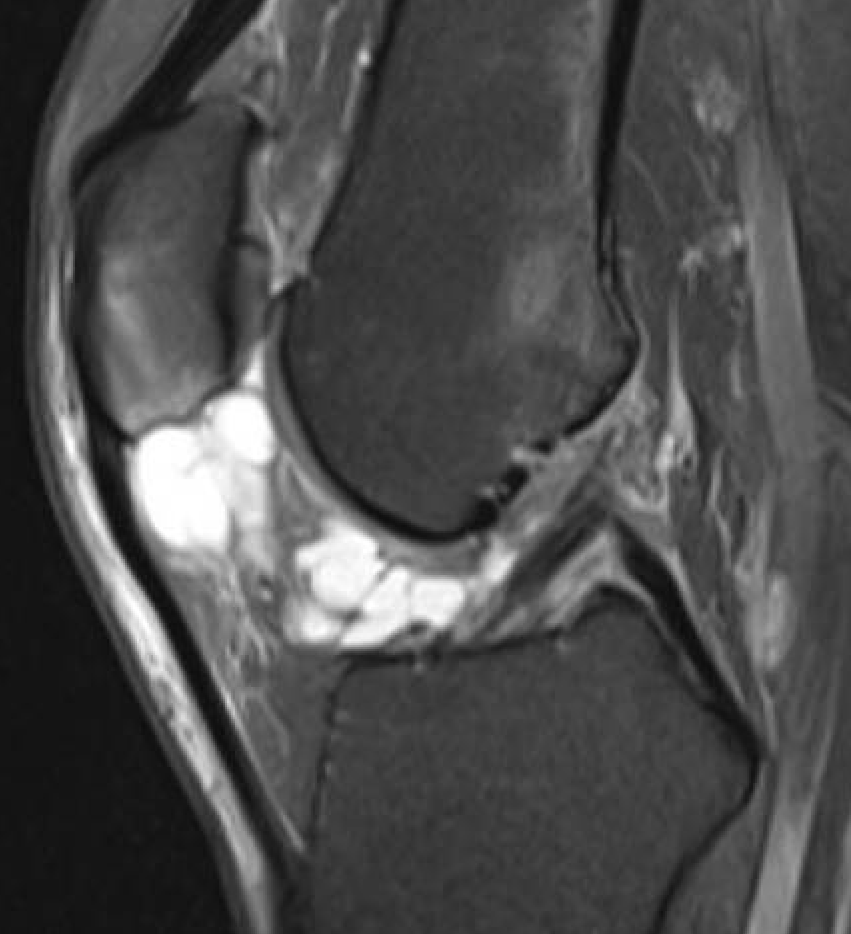

www.boneschool.com/knee-cruciate-ligament-ganglion

Cystic structure lined by a mature capsule of dense fibrous tissue

- contains thick viscous fluid with a high mucopolysaccharide content

- fluid is a myxoid degeneration of synovial fluid